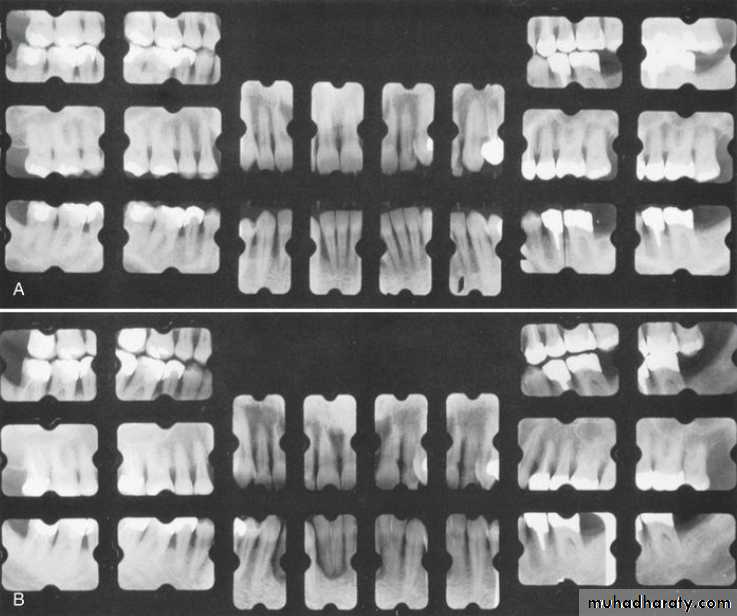

Radiographic examination must be individualized, depending on the initial severity of the case and the findings during the recall visit. These are compared with findings on previous radiographs to check the bone height and look for repair of osseous defects, signs of trauma from occlusion, periapical pathologic changes, and caries.